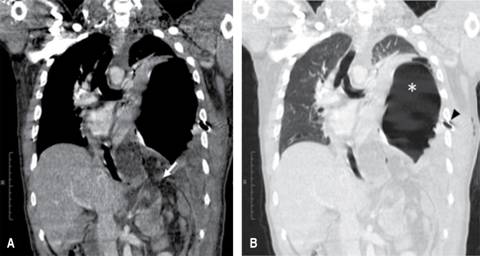

Figura 2: Corte coronal de TC en fase contrastada con ventana mediastinal (A) y pulmonar (B) que muestra defecto de continuidad en cúpula diafragmática izquierda de 3.5 cm (flecha) por donde protruyen estómago(*) y grasa mesentérica, condicionando desplazamiento de estructuras del mediastino hacia la derecha. Presencia de sonda pleural que penetra por sexto espacio intercostal izquierdo (punta de flecha).